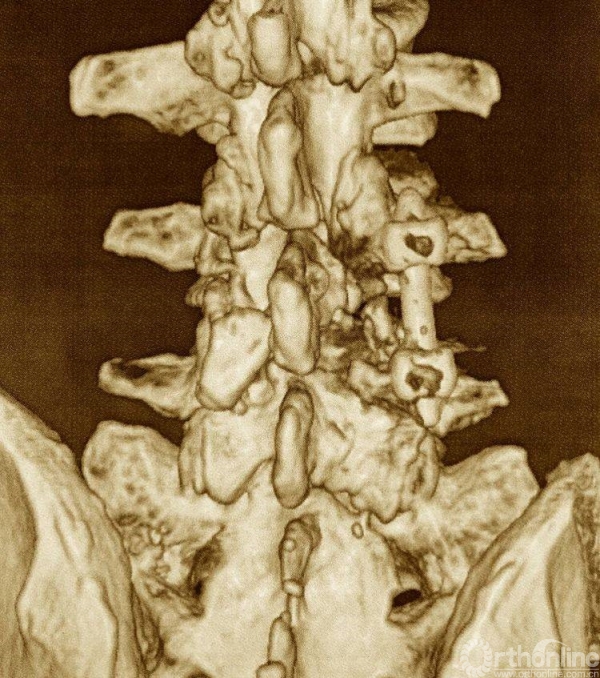

术后三维CT资料